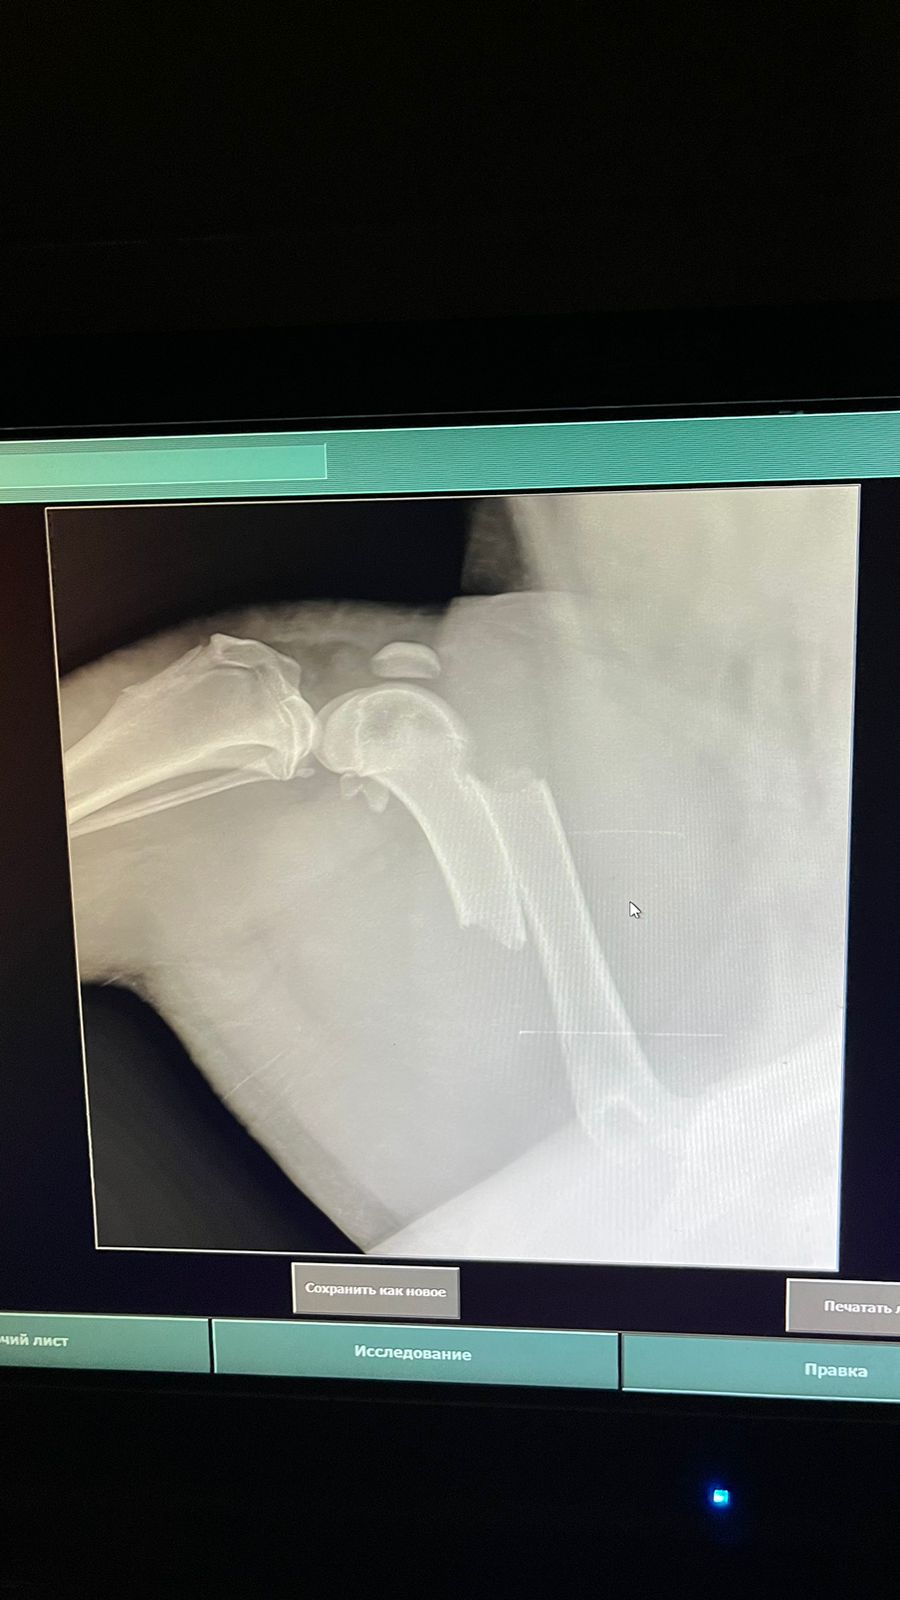

Волонтёр привела молодую суку ризена со сломанной лапой в клинику к Насте pani Stasi. Вроде перелом не сильно свежий.

Ногу будет хирург смотреть и может в ближайшее время прооперируют.

Собаке 8 месяцев, хозяйка попала в реанимацию.

Её забрала заводчица. И что-то там у них случилось, то ли лошадь понесла, то ли что, в общем, собака перепрыгивала через телегу и сломала лапу. У заводчицы тоже ключица сломана, может ещё что-то.

Ветеринар позвонила знакомому волонтёру, говорит, чего усыплять, я её соберу, рентген только надо.

Операцию сделали, собрали лапу на две пластины. Выписка попозже будет.

Да, задняя правая сломана.